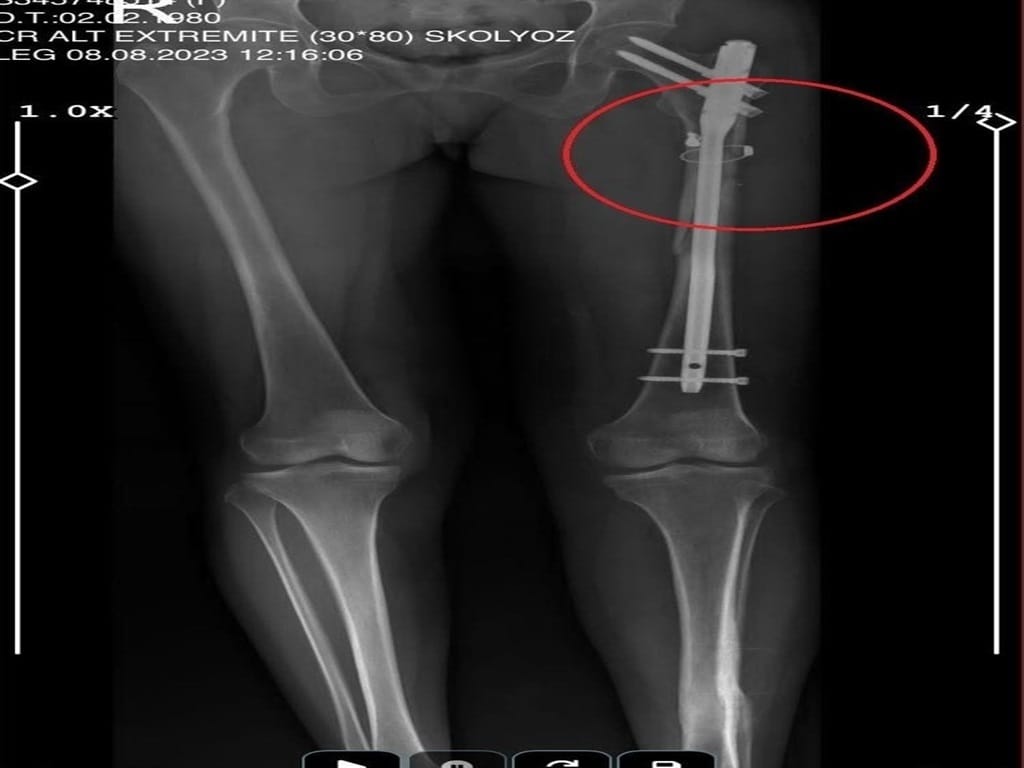

Saldırgan, aynı silahla sevgilisi Fatma O.’yu da 8 kurşunla yaraladı. Olayın ardından evin içinde tam bir kabus yaşandı. Arkadaşının cesedini önce çarşafa, ardından kokmasın diye streç filme sarıp bantlayan Sarıkaya, yaralı sevgilisini hastaneye götürmek yerine eczaneden aldığı malzemelerle evde tedavi etmeye çalıştı. Fatma O., yaralı haldeyken 21 gün boyunca evde rehin tutuldu ve bu süre zarfında defalarca cinsel saldırıya uğradı.